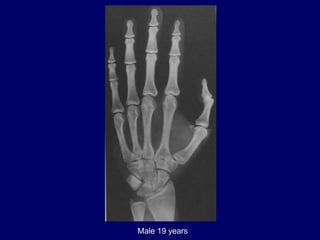

Male 19 years